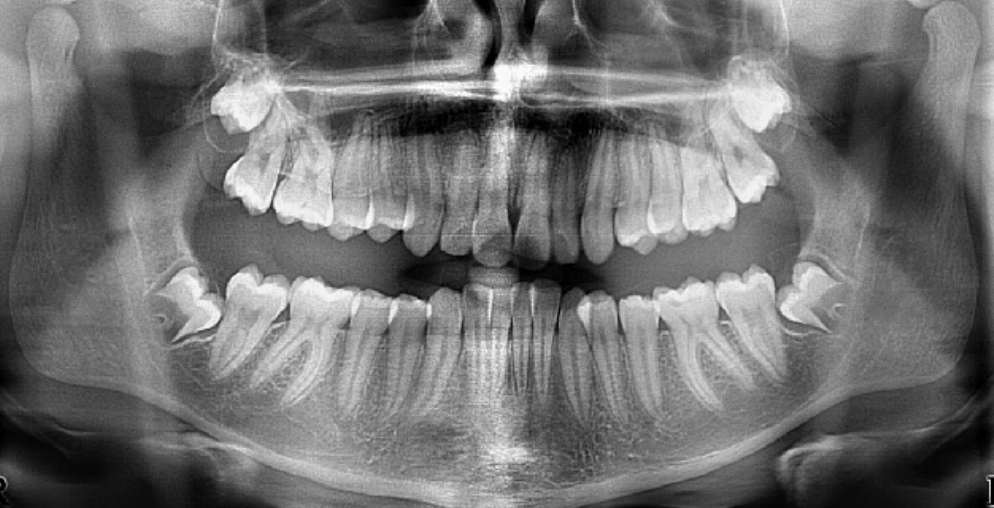

The age in this picture is characterized by the teeth erupted which are: Maxilla ABCDE and Mandible ABCDE. The teeth unerupted are the Maxilla 1234567 and the Second molar in the Maxilla- 1/3 Crown completed, Mandible- 1/3 crown completed

At age 6 is characterized by the erupted first molar in the maxilla, and the erupted central incisor and first molar in the mandible. Teeth erupted – Maxilla ABCDE6, Mandible 1BCDE6 - Teeth unerupted – Maxilla 123457, Mandible 23457

Dental age 7 is characterized eruption of permanent teeth Mandibular Lateral Incisor, Maxillary Central Incisor

Dental age 8 is characterized by eruption of the maxillary lateral incisors

Teeth erupted – Maxilla 12CDE6, Mandible 12CDE6

Teeth unerupted – Maxilla 3457, Mandible 3457